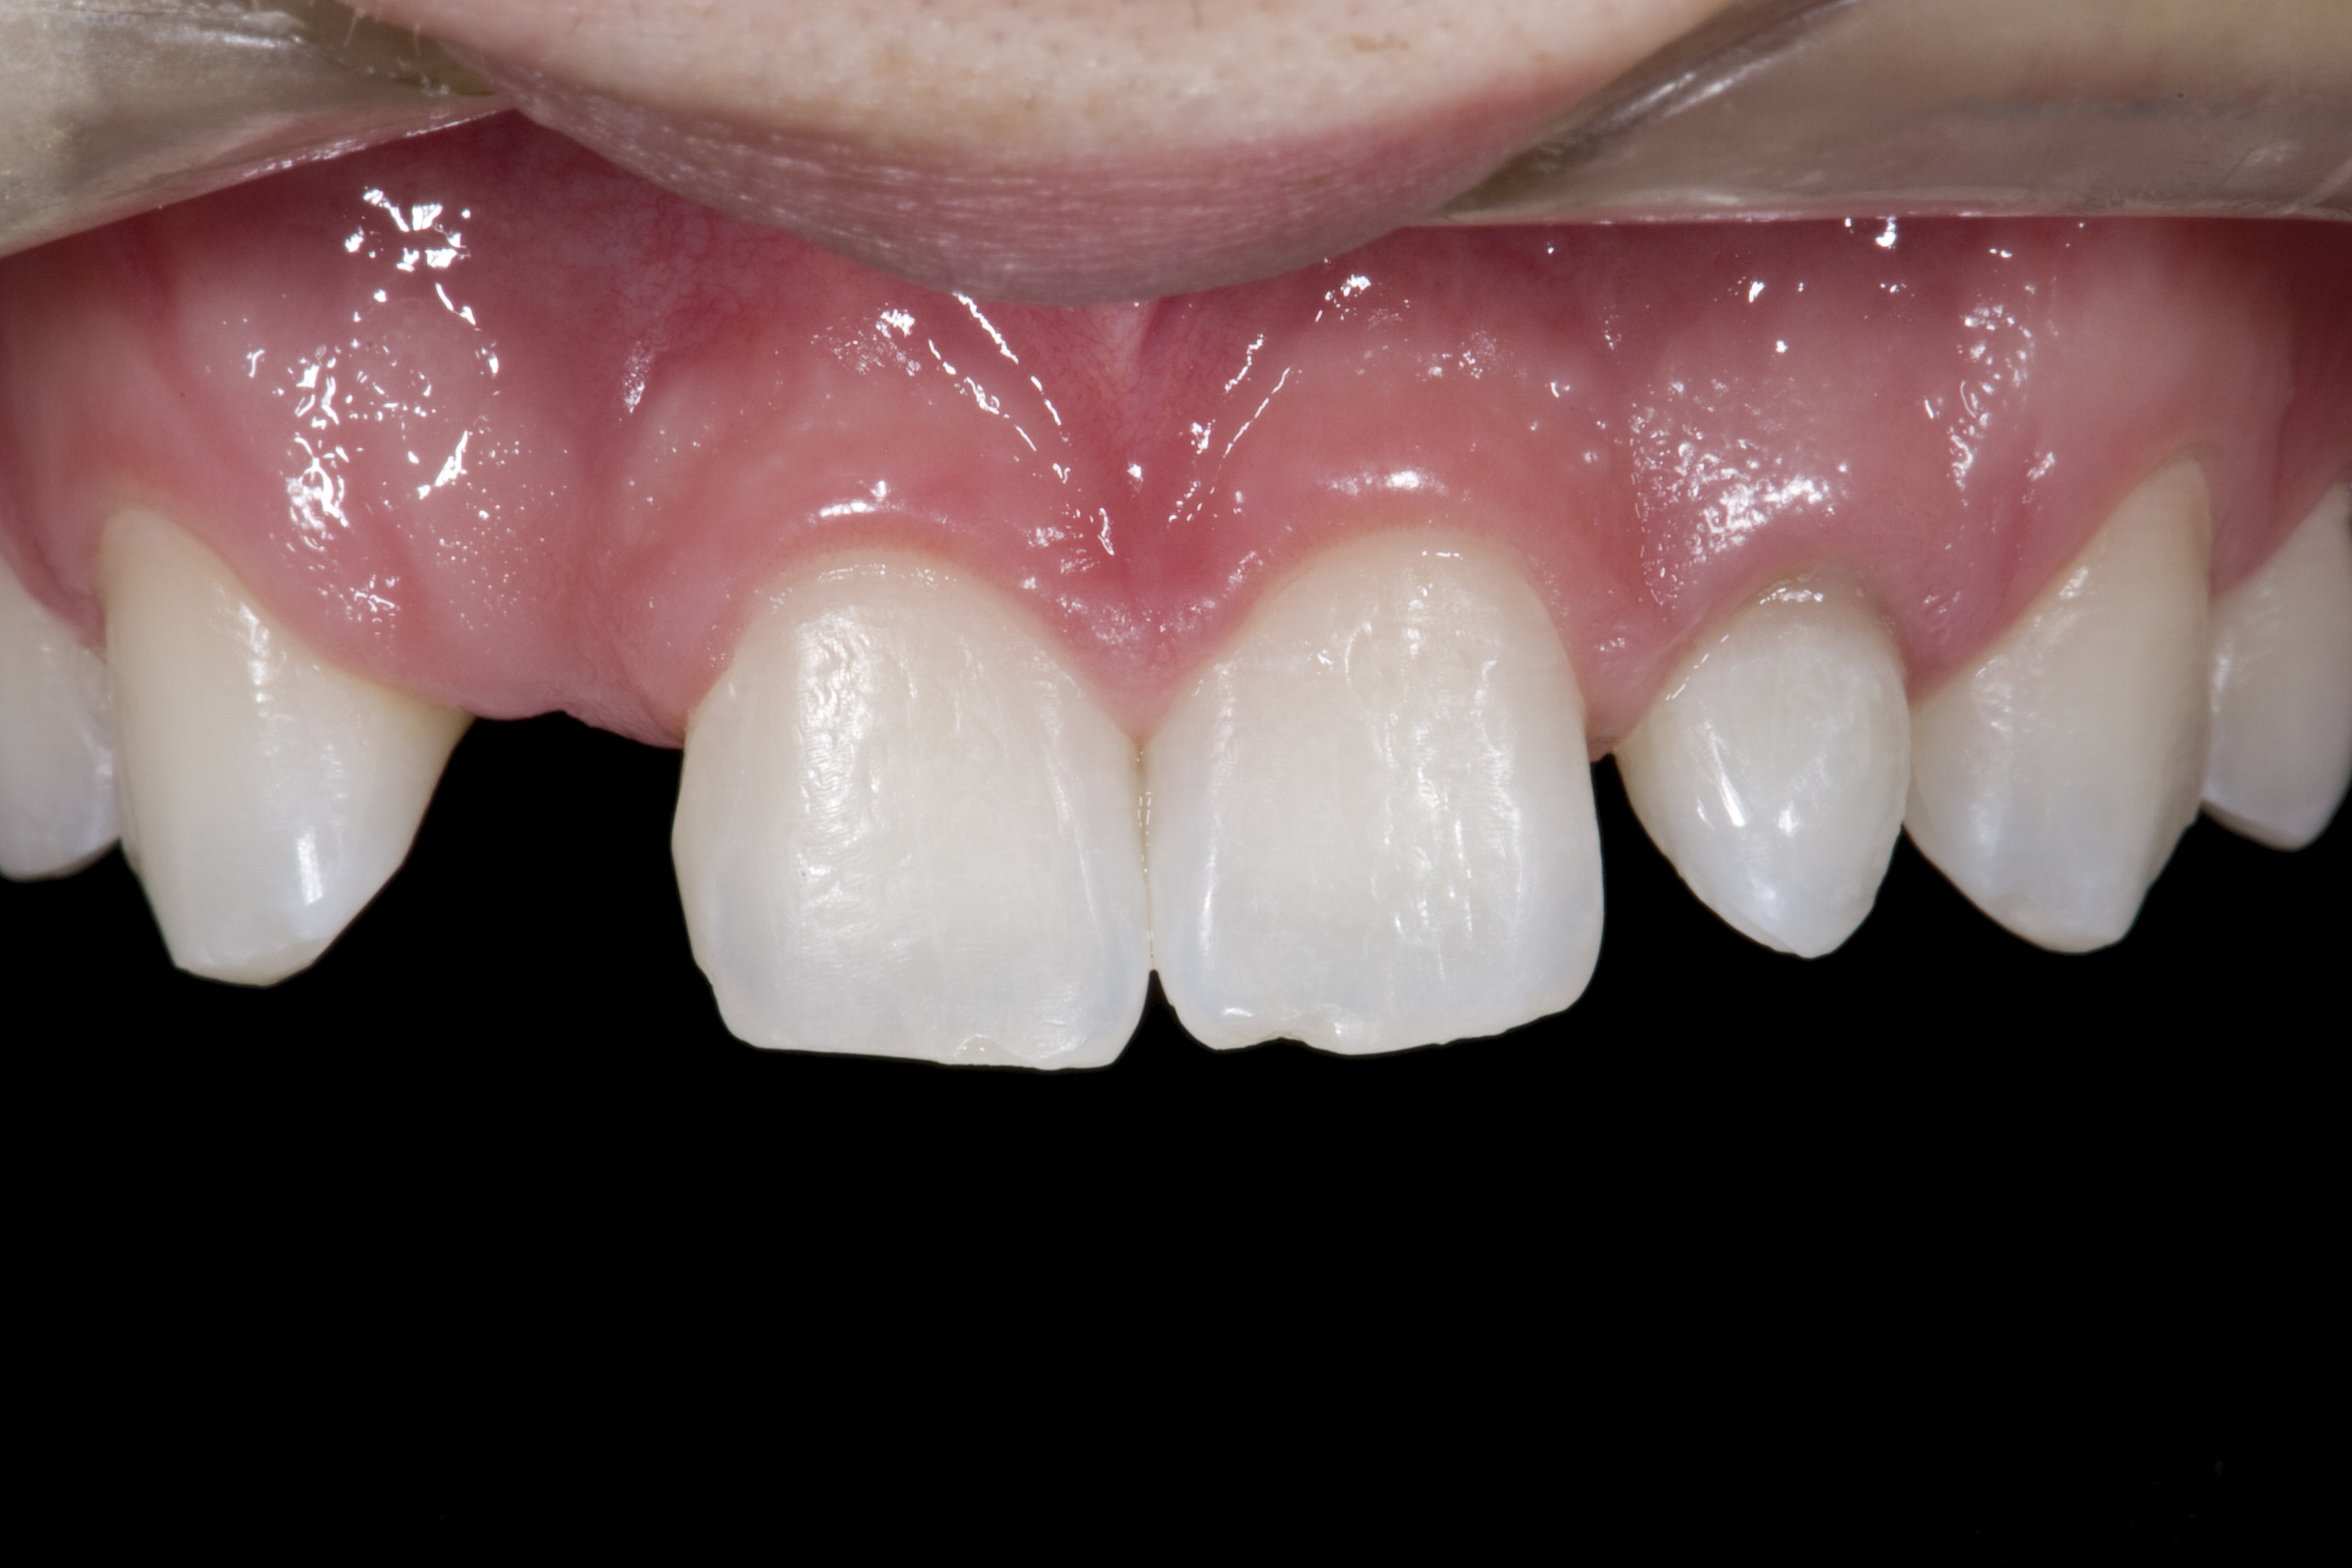

Some patients do not want an implant due to the need for surgical intervention, and others may not have enough space for implant placement. A 15-year-old patient presented to the office after completion of orthodontic treatment to idealize the spacing of her teeth and improve her occlusal relationship (Figure 12 through Figure 14). Because both of her maxillary lateral incisors were missing, the patient was wearing a retainer with lateral incisor pontics. She had a busy school schedule, but expressed her desire for a fixed restorative option. All of her options were discussed, and the patient was informed that if she wanted an implant, she would have to wait for at least 3 to 4 years for completion of growth. The patient was not sure if or when she wanted to have an implant placed in the future, especially considering her busy schedule and desire to attend college after high school. Considering her age and the need to be conservative, a single-wing zirconia Maryland Bridge was chosen as the ideal prosthetic replacement option. Because bonding a non-etchable and smooth surface such as zirconia requires chemical adhesion, it was decided to use a modified technique to make the bridge more retentive. One of the ways to improve adhesion of a zirconia bridge is to use an etchable feldspathic ceramic layer on the internal surface of the zirconia retainer.56-58 Unfortunately, it can be difficult to determine the thickness of the ceramic and ensure accurate seating of the restoration.

(12.) 15-year-old girl after orthodontic therapy idealized maxillary lateral incisor spaces.

Figure 12

(13.) Deficient ridges in the areas of the missing lateral incisors.

Figure 13